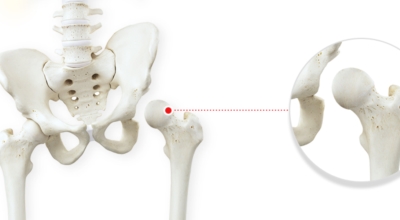

고관절이란 골반을 지탱하는 관절로서 근육과 힘줄로 구성되어 있어요. 학계에서는 고관절을 엉덩이 관절이라고 부르기도 하며 인체의 하중을 지탱하는 아주 중요한 관절입니다. 각별히 고관절은 우리가 정상적으로 서있거나 움직일 수 있게 만들어주며 달리기, 점프, 무거운 무게를 들 때 최대 체중의 2~10배 가량의 하중을 받기 때문에 적절한 관리가 필요합니다. 오늘은 고관절에서 일어날 수 있는 고관절 통증 증상에 관해서 알려드리도록 하겠습니다.

고관절염은 고관절에 나타나는 관절염을 말하며 고관절의 연골이 닳게 되면서 뼈와 뼈가 서로 부딪히며 통증을 일으키게 돼요. 고관절염 초기 증상으로는 사타구니 부위가 불편하게 느껴지며, 무리하면 통증이 발생할 수 있으며, 관절염 증상이 심해지면서 사타구니에서 느끼던 통증이 허벅지와 엉덩이 통증으로 이어지기도 하는데, 고관절염 통증 증상으로 초기에는 허리 통증이 나타나 허리 질환과 혼동하기 쉬우며 각별히 척추질환이 있는 사람은 고관절 통증과 마찬가지로 엉덩이, 다리 통증이 동반되기 때문에 훨씬 헷갈리는 경우가 많습니다.